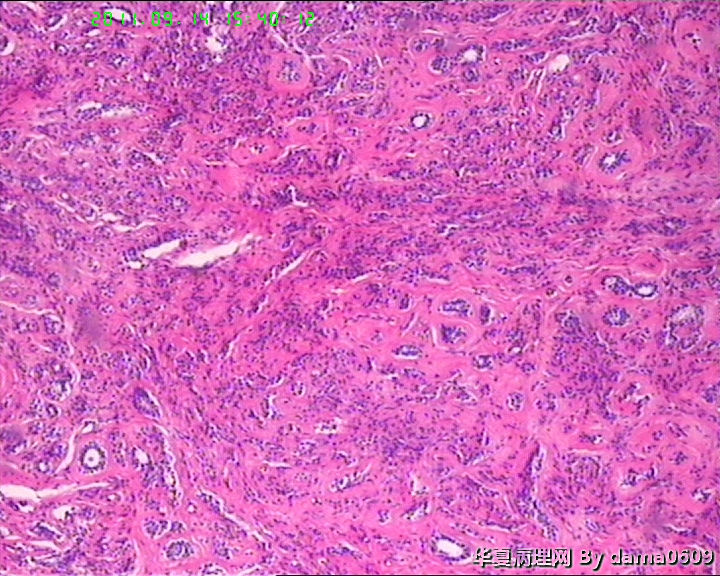

女,22岁,乳腺肿物,病史不详。

不整形软组织肿物一个,V:2.0x1.5x1.5cm。无包膜。切面实性,灰白色,小结节状,质中。

镜下结构复杂,图3、4、8、10、11、12、13、15、17、18、19、20为肿物中央区域,占标本大部分,图1、2、7、14为肿物边缘部分,图5、6、9、16、21为二者交界处。有点乱,不好意思,请老师别介意。

请教老师,诊断:硬化性腺病,可以吗??谢谢!!